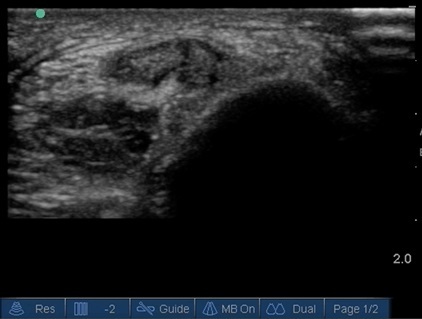

Bild: Fuß und Sprunggelenk, Dynamische Ultraschalluntersuchung bei einer Sehnenruptur des Peroneus brevis